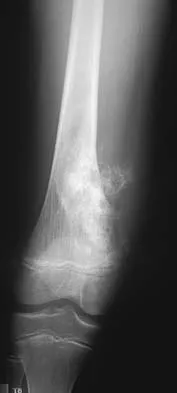

Examination of an obese 3-year-old girl reveals 30 degrees of unilateral genu varum. A radiograph of the involved leg with the patella forward is shown in Figure 10. Management should consist of

Explanation

The clinical scenario describes infantile tibia vara (Blount's disease). The radiograph shows severe deformity with the characteristic Langenskiold stage 3 changes of the medial proximal tibial metaphysis that distinguish it from physiologic bowing. The preferred treatment is proximal tibiofibular osteotomy with acute correction into slight valgus to unload the damaged area of the physis. This method provides the best results in patients younger than age 4 years. Continued observation would result in progressive deformity. Bracing is most effective in younger children with less severe deformity. Lateral proximal tibial hemiepiphysiodesis relies on growth of the injured medial physis for correction and would result in severe tibial shortening in this young child. Complete epiphysiodesis also produces severe shortening and requires multiple lengthening procedures. Johnston CE II: Infantile tibia vara. Clin Orthop 1990;255:13-23.